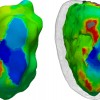

A Statistical Study of the Cardiac Diffusion Tensor Images

While the main geometrical arrangement of myofibers has been known for decades, its variability between subjects and species still remains largely unknown. Understanding this variability is not only important for a better description of physiological principles but also for the planning of patient-specific cardiac therapies. Furthermore, the knowledge of the relation between the myocardium shape and its myofiber structure is an important and required stage towards the construction of computational models of the heart since the fiber orientation plays a key role when simulating the electrical and mechanical function of the heart. The knowledge about fibre orientation has been recently eased with the use of Diffusion Tensor Imaging (DTI) since there is a correlation between the myocardium fibre structure and diffusion tensors. DTI also has the advantage to provide directly this information in 3D with a high resolution, unfortunately it is not available in vivo due to the cardiac motion. A statistical study of ex vivo cardiac DTI will help in understanding the cardiac fibre structure and in modeling the electromechanical behavior of the heart.

While the main geometrical arrangement of myofibers has been known for decades, its variability between subjects and species still remains largely unknown. Understanding this variability is not only important for a better description of physiological principles but also for the planning of patient-specific cardiac therapies. Furthermore, the knowledge of the relation between the myocardium shape and its myofiber structure is an important and required stage towards the construction of computational models of the heart since the fiber orientation plays a key role when simulating the electrical and mechanical function of the heart. The knowledge about fibre orientation has been recently eased with the use of Diffusion Tensor Imaging (DTI) since there is a correlation between the myocardium fibre structure and diffusion tensors. DTI also has the advantage to provide directly this information in 3D with a high resolution, unfortunately it is not available in vivo due to the cardiac motion. A statistical study of ex vivo cardiac DTI will help in understanding the cardiac fibre structure and in modeling the electromechanical behavior of the heart.

Non invasive cardiac personalisation

Non invasive cardiac personalisation

Simulation of ventricular tachycardia re-entry circuit

Simulation of ventricular tachycardia re-entry circuit

heartMeshFine

heartMeshFine

Electrophysiology

Electrophysiology

Cardiac Fibres from in vivo Diffusion Tensor Imaging

Cardiac Fibres from in vivo Diffusion Tensor Imaging